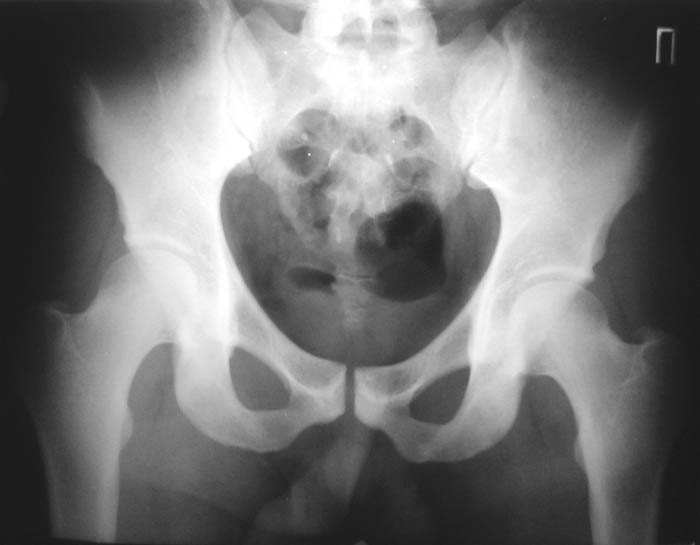

Уважаемые коллеги!Окажите, пожалуйста, консультативную помощь.Мужчина, 24 года. Туберкулез крестцово-подвздошного сочленения справа,

активная фаза. Болен в течение 6 месяцев. Проходил курсы НПВС - без эффекта.Жалобы на постоянные боли в поясничной области. Местно: крестцовая область припухшая, кожа не изменена, при пальпации боль, осевая нагрузка - боль, хромота на правую ногу.Общие анализы - без особенностей.МРТ 09.11.03. - патологических изменений в поясничном отделе не выявлено.Описание рентгенолога: остеосклероз, нечеткость контуров, участки деструкции в правом крестцово-подвздошном сочленении.Положительный анализ на антитела к микобактериям (IgM+E) от 16.10.03.Вопросы: уточнение диагноза, определение тактики лечения.С уважением,А.В.ВладзимирскийДонецкий НИИ травматологии и ортопедииДонецк, Украина

"Представленные рентгенограмы не убедительны с точки зрения наличия деструктивного процесса в крестцово-подвздошном сочленении. Необходимо выполнить компьютерную томографию таза с обязательным захватом крестцово-подвздошных сочленений. Желательно также знать рентгенологическую картину легких."